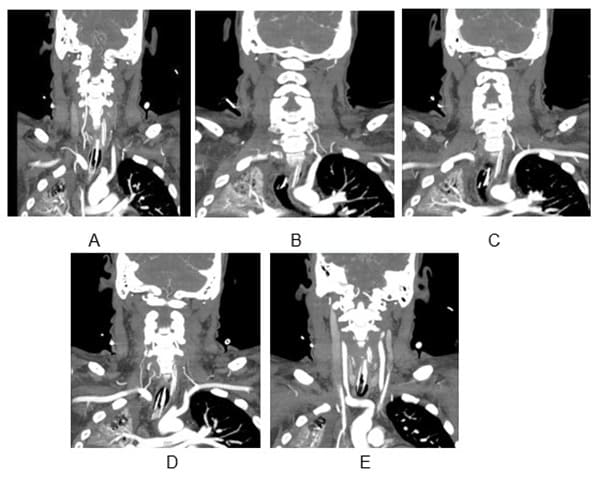

We present the case of a 30-year-old previously healthy man who presented to the ER on a Sunday morning with acute onset difficulty breathing and weakness in his extremities. He spent most of Friday and Saturday with friends. Earlier that morning he had complained of neck pain and tingling in his hands, which prompted his roommate to bring him to the ER. He was able to walk into the ER, soon after he required assistance to stand up. He now reported, “I can’t move” and “I can’t breathe, I want oxygen”. This was followed by agitation, respiratory distress (Oxygen saturation at 31%) requiring intubation and mechanical ventilation. There was no history of trauma, recent surgical procedures, diabetes, hypertension, heart disease, other significant past medical conditions, and no recent travel history. His vital signs showed normothermia soon followed by hypothermia returning to normothermia (98-degree F; dropping to 94-degree F and 98-degree F over 3 hours), BP 160/98 (then 116/61; followed by 56 mm Hg systolic that improved with fluid boluses. Heart rate was 66/min and later 36/min improving to 80s (36-137 range); EKG showed alternating sinus rhythm and atrial fibrillation with rapid ventricular rate. On day 2 patient failed extubation due to very low tidal volume (80 ml). Chest CT did not show any pathology to explain respiratory failure. His exam revealed quadriplegia and this led to a neurology consultation. Neurological examination showed intact consciousness; he responded to loud verbal and physical stimulation with nods or head shaking. Eye movements initially showed dysconjugate gaze (this resolved in 24 hours), patient exhibited flaccid (0/5) quadriplegia, areflexia and down-going plantar response. He however managed to dislodge the endotracheal tube (ETT) with his tongue movements multiple times. He had normal sensation in his face; below his neck, he had decreased sensation to temperature and pain, but intact light touch and proprioception. Head CT did not show any acute abnormalities. Other investigations on admission revealed normal CBC, CMP; urine drug screen was positive for THC and negative for stimulants, blood EtOH level was < 3. Additional tests included CSF analysis with cell count of 7, normal protein and glucose. CSF culture later came back negative, and he had a normal sed rate (ESR). Brain MRI revealed numerous subcentimeter bilateral cerebellar, posterior temporal and occipital embolic infarcts (Figure 2 A- 2E and Figure 3). Magnetic Resonance Imaging of the cervical spine showed T2 hyperintensity in the territory of the anterior spinal artery extending from C2 to C6 (Figure 1). MRA of the head and neck were normal (Figure 4A and 4B). Transthoracic Echocardiography showed normal ejection fraction, no intracardiac structural abnormalities and no right to left shunt. Transesophageal echocardiography did not reveal any abnormalities in the proximal aorta. CT angiography of head and neck done few days later was normal as well indicating no occlusions or dissections (Figure 5A-5E). He received 1-gram intravenous solumedrol daily for five days based on initial cervical MRI findings in addition to aspirin started after MRI showed acute infarcts. His CSF also showed 14 oligo clonal bands (unclear significance likely secondary to acute ischemia). Hospital course – On day 3 he went into neurogenic shock and multiple episodes of vasovagal bradycardia (HR in the 40s) and demonstrated hemodynamic instability when he was being moved by nursing staff. His exam now showed intact cognition and normal cranial nerve examination. He developed ileus and had frequent episodes of bradycardia (Figure 6), fluctuating blood pressure all part of autonomic dysfunction causing the nurses to panic. He required transvenous pacemaker which was soon replaced with permanent pacemaker. After four weeks his tidal volume improved from 80 ml to 240 ml., he started to regain significant strength in his lower extremities to the point where he was able to stand up and walk up to 25 feet when his vital signs permitted. His upper extremities remained flaccid, areflexic except for his ability to close his hands to gently squeeze a soft ball. Repeat labs including spinal fluid showed similar findings including 14-oligoclonal bands, normal cell count, protein, and glucose. West Nile virus IgM, HTLV-1, HIV, HSV and CSF VDRL testing were all-negative. After eight weeks, his autonomic instability continued to improve and so did his participation in physical therapy sessions. He could now ambulate up to 100 feet using a special walker; however, he remained flaccid in his upper extremities and continued to need intermittent daily ventilator support due to tidal volume at ~300ml. Repeat MRI of his brain and spinal cord was placed on hold due to his pacemaker that requires many weeks for lead maturation.

Figure 5A: 5E-CTA neck done few days later showing intact vasculature.